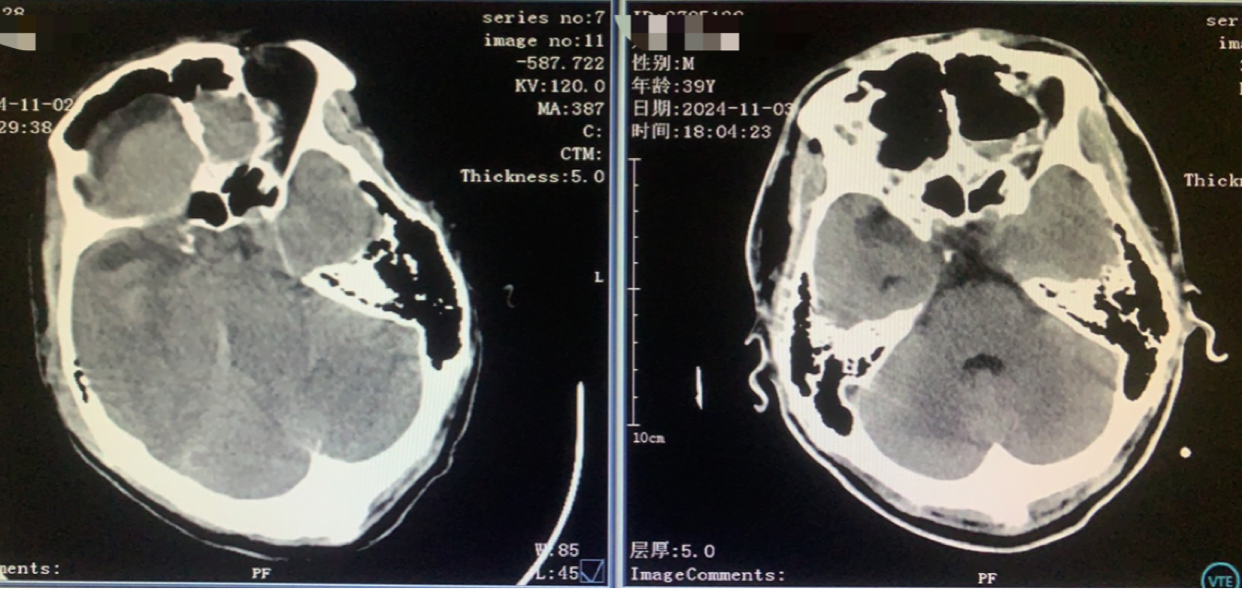

术前CT

神志昏迷双瞳散大对光反射迟钝入院,入院后甘露醇脱水加地米静滴后患者神经功能有改善,能摸索定位,瞳孔反射改善。考虑占位大直接切除可能出血多,拟术前栓塞处理,但造影发现栓塞不易风险高后放弃栓塞。

双侧入路计划(为降低优势半球损伤风险先右侧处理,实在不好搞再左侧)

从右额分块切除处理大部分后,因条件所限单侧入路风险高遂加开左侧额外侧(骨窗较右侧小)。

术前术后对比